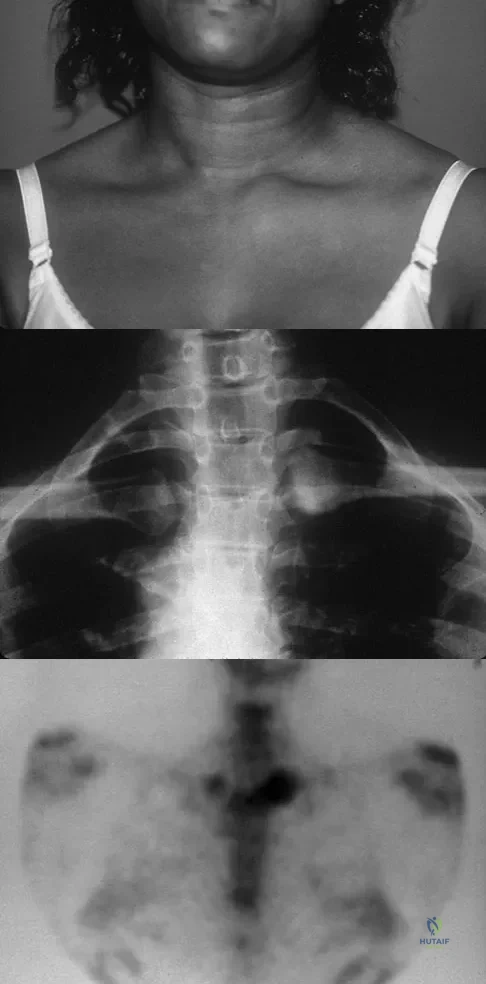

A 52-year-old woman reports mild pain localized to the left sternoclavicular joint. History is notable for chronic renal failure requiring dialysis for the last 5 years. A clinical photograph, chest radiograph, and bone scan are shown in Figures 58a through 58c. What is the most likely diagnosis?